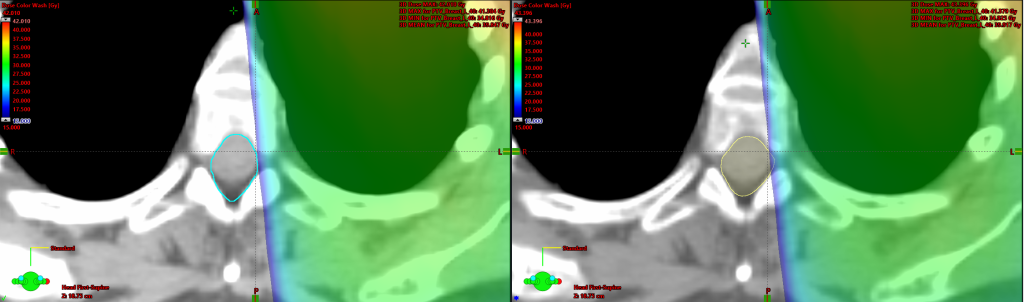

Ved dosimetriske forskjeller, så vi på avviket mellom dosen til den kliniske strukturen og dosen til KI-inntegnede strukturen. Naturligvis så vil eventuelle avvik kunne forklares gjennom geometriske forskjeller. Et eksempel er vist på bildet under hvor bildet til venstre er fra klinisk plan, mens den til høyre er KI-inntegnet:

På bildet her så ser man et zoomet inn bilde av spinalkanalen i det transversalplanet. Spinalkanalen er serielt organ, som betyr av hvis man ødelegger en liten del av den, så ødelegger man hele. På bildet så ser man til tross for et lite geometrisk avvik, så vil maksdosen til spinalkanalen være høyere på bildet til høyre.